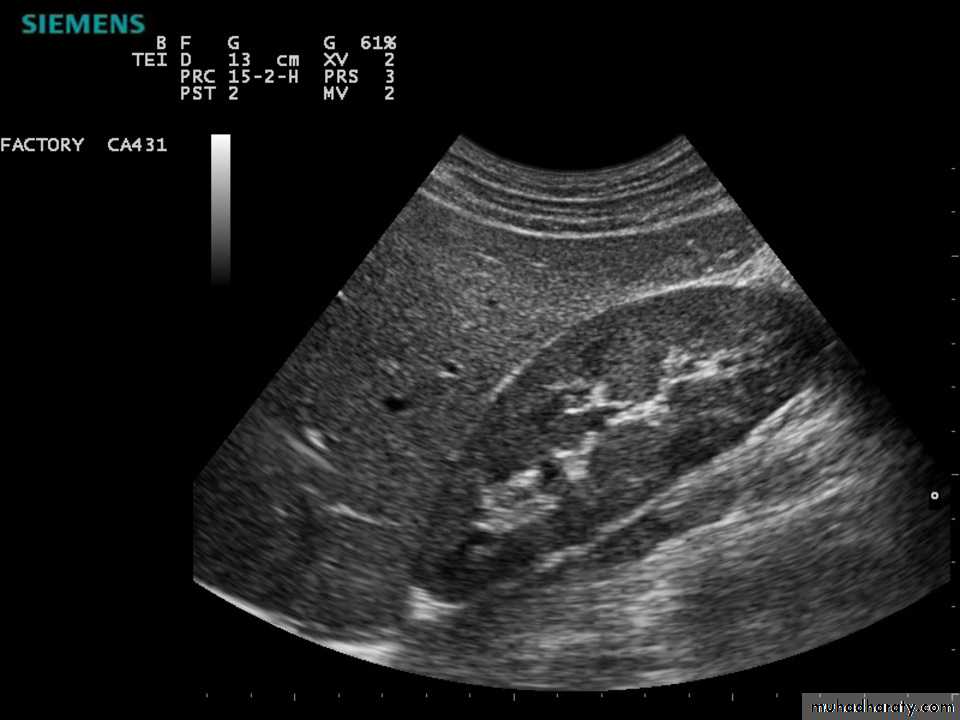

Simple renal cyst with acoustic enhancement